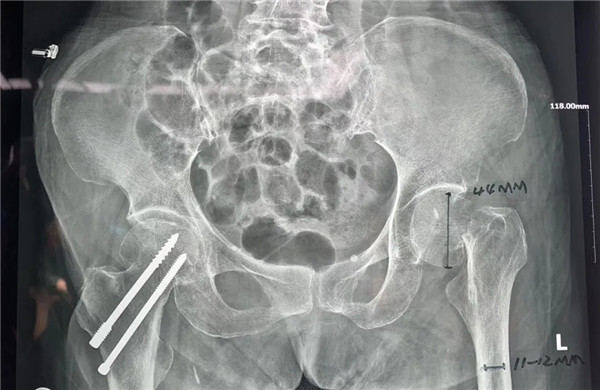

家人趕快第一時(shí)間將她送至我院,經(jīng)拍片后診斷為:左髖股骨頸頭下型骨折,病人入住關(guān)節(jié)科病區(qū)。

確定手術(shù)后,經(jīng)內(nèi)科、麻醉科、超聲科等專(zhuān)家會(huì)診后,王老太太符合手術(shù)指征,3月5日,老太太接受了股骨頭置換手術(shù)。